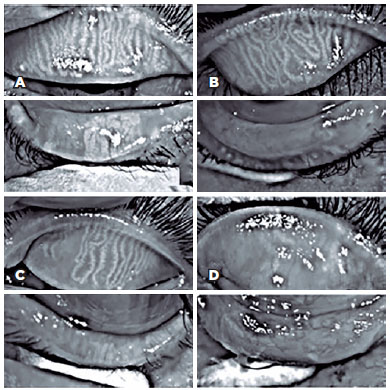

In this study, 27 patients underwent meibography, 24 of them in both eyes, and 3 in only one eye, totaling 51 eyes. The meiboscore was abnormal (≥2) in the upper eyelid of 8 (29.6%) patients and in the lower eyelid of 17 patients (62.9%) (Figure 3).

Previous studies on ocular surface changes have reported signs of dry eye disease in 38%-100% of patients based on the methods used for assessment such as the tear film breakup time or Schirmer's test(5,20,21). MGD signs were recorded as an abnormal meiboscore (<2) in 60% and 56% of the upper and lower eyelids, respectively(22). To our knowledge, such studies have not been reported previously. The severity of MGD (abnormal meiboscores) correlated significantly with age (p=0.001), worsening by 12% for each 1-year increase in age. Such a relationship probably reflects cumulative exposure to UVR, an important known risk factor of clinical manifestations and disease severity in patients with XP(23).